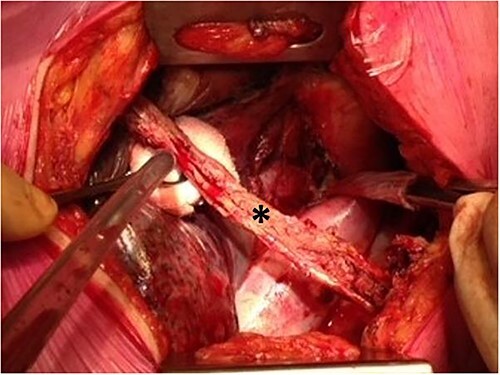

The aim of this study was to evaluate the surgical treatment of esophago-tracheobronchial fistulas (ETBFs) that occurred after esophagectomy with gastric conduit reconstruction in a tertiary referral center for esophageal surgery. All patients who underwent surgical repair for an ETBF after esophagectomy with gastric conduit reconstruction were included in a tertiary referral center. The primary outcome was successful recovery after surgical treatment for ETBF, defined as a patent airway at 90 days after the surgical fistula repair. Secondary outcomes were details on the clinical presentation, diagnostics, and postoperative course after fistula repair. Between 2007 and 2022, 14 patients who underwent surgical repair for an ETBF were included. Out of 14 patients, 9 had undergone esophagectomy with cervical anastomosis and 5 esophagectomy with intrathoracic anastomosis after which 13 patients had developed anastomotic leakage. Surgical treatment consisted of thoracotomy to cover the defect with a pericardial patch and intercostal flap in 11 patients, a patch without interposition of healthy tissue in 1 patient, and fistula repair via cervical incision with only a pectoral muscle flap in 2 patients. After surgical treatment, 12 patients recovered (86%). Mortality occurred in two patients (14%) due to multiple organ failure. This study evaluated the techniques and outcomes of surgical repair of ETBFs following esophagectomy with gastric conduit reconstruction in 14 patients. Treatment was successful in 12 patients (86%) and generally consisted of thoracotomy and coverage of the defect with a bovine pericardial patch followed by interposition with an intercostal muscle.

本研究的目的是评估一家三级食管外科转诊中心对食管胃导管重建术后食管气管支气管瘘(ETBF)的手术治疗。该三级转诊中心纳入了所有在食管切除术和胃导管重建术后因 ETBF 而接受手术修复的患者。主要结果是 ETBF 手术治疗后的成功康复,即手术修复瘘管后 90 天气道通畅。次要结果是瘘管修补术后的临床表现、诊断和术后疗程的详细情况。2007 年至 2022 年间,共有 14 名患者接受了 ETBF 手术修复。14 名患者中,9 人接受了食管切除术并进行了颈部吻合术,5 人接受了食管切除术并进行了胸内吻合术,术后 13 人出现了吻合口漏。手术治疗包括:11 名患者采用开胸手术,用心包补片和肋间肌瓣覆盖缺损处;1 名患者采用补片,但未插入健康组织;2 名患者通过颈部切口仅用胸肌瓣修复瘘管。手术治疗后,12 名患者痊愈(86%)。两名患者(14%)因多器官功能衰竭而死亡。这项研究评估了 14 名患者在食管切除术后进行胃导管重建手术修复 ETBF 的技术和效果。12 名患者(86%)的治疗取得了成功,一般包括开胸手术和用牛心包补片覆盖缺损,然后用肋间肌进行插补。